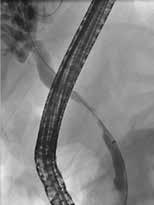

Obstruksjon av pankreas hovedgang Årsaken til smerter ved kronisk pankreatitt er multifaktoriell men kan hos mange, spesielt i tidlig fase av tilstanden (før pasienten blir opiatavhengig), forklares helt eller delvis av økt trykk i pankreas hovedgang på grunn av obstruksjon av fløde av pankreassaft. Obstruksjonen er oftest forårsaket av strikturer og konkrementer i caput eller collum og gir dilatasjon av hovedgangen. Obstruksjon lenger oppstrøms i corpus og cauda har sjeldnere klinisk relevans. Den vanlige og minst invasive tilnærmingen er å plassere en plaststent forbi obstruksjonen i hovedgangen som trykkavlastning for å se om dette bedrer smertene. Dersom effekt kan man fortsette stentbehandling og evt. gå videre med andre invasive tiltak. ESGEs retningslinje fra 2018 foreslår endoskopisk terapi og/ eller ekstrakorporal sjokkbølge-litotripsi (ESWL) som førstevalg for smertefull, kronisk pankreatitt med obstruerende konkrement og dilatasjon av hovedgang i caput eller corpus. Imidlertid viste ESCAPE-studien fra 2020 og en senere langtids oppfølgingsstudie at tidlig (opiatavhengighet < 6 mnd.) kirurgi var bedre enn endoskopisk behandling i å gi smertelindring både på kort og lang sikt. Pasienter operert tidlig hadde også mindre reintervensjoner enn pasientene med endoskopisk behandling. Nyere retningslinjer fra ASGE (2024) anbefaler derfor tidlig MDT vurdering med tanke på kirurgi. Det er imidlertid mange faktorer som påvirker valg av terapi, inklusiv pasientens ønske, komorbiditet og alder, og all invasiv (endoskopi/kirurgi) behandling har dårligere effekt jo lenger ut i sykdomsforløpet man har kommet. Tidspunkt for intervensjon kan være like viktig som valg av prosedyre, og beslutning om valg av terapi krever ekspertise og nøye risikovurdering i hvert enkelt tilfelle. All endoskopisk intervensjon på pankreas er beheftet med komplikasjoner som post-ERCP pankreatitt, blødninger, perforasjon og infeksjon. Pasienter med kronisk pankreatitt har dessuten økt risiko for adenocarcinom i pankreas som er en viktig differensialdiagnose ved dilatasjon av pankreas hovedgang eller forverring av symptomer hos pasienter med kronisk pankreatitt.

Små konkrementer i pankreas hovedgang (< 5 mm) kan ofte fjernes endoskopisk ved at strikturer dilateres og konkrementet hentes

ut med konvensjonelle metoder (Fig 4). Større konkrementer er mer krevende og kan behandles med ESWL eller pankreatikoskopi og fragmentering av konkrement(ene) med sjokkbølgelitotripsi eller laser. Selv om man tilsynelatende klarer å fjerne alle konkrementer fra hovedgangen er tilbakefallsfrekvensen høy og pasientene risikerer langvarig stentbehandling (vanligvis en eller flere plaststenter) og gjentatte endoskopiske prosedyrer.

Standard behandling av benigne strikturer har vært ERCP med gjentatte dilatasjoner og innleggelse av multiple plaststenter i gallegang over en periode på ett år (Fig 5). De senere år har bruk av selvekspanderende metallstent i 6-12 mnd. blitt mer vanlig dersom forholdene teknisk ligger til rette for dette. Det er imidlertid risiko for residiv av striktur på grunn av progresjon av grunntilstanden så gjentatt endoskopisk behandling kan bli nødvendig.